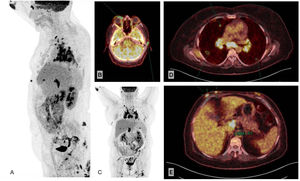

Additional TestsThe laboratory workup was remarkable for a negative result in the interferon γ release assay and increased levels of angiotensin-converting enzyme (116U/L [reference range, 13–63.9]). Positron-emission tomography–computed tomography (PET–CT) confirmed the presence of matted lymph nodes with considerably increased uptake in the mediastinum, supraclavicular fossae, and retroperitoneum (Fig. 3A–C), together with 3 pulmonary nodules (Fig. 3D). We also observed subcutaneous nodules with heavily increased uptake at the abovementioned locations and in the mammary and intergluteal regions (Fig. 3B–D), with a maximum standard uptake value of 6.